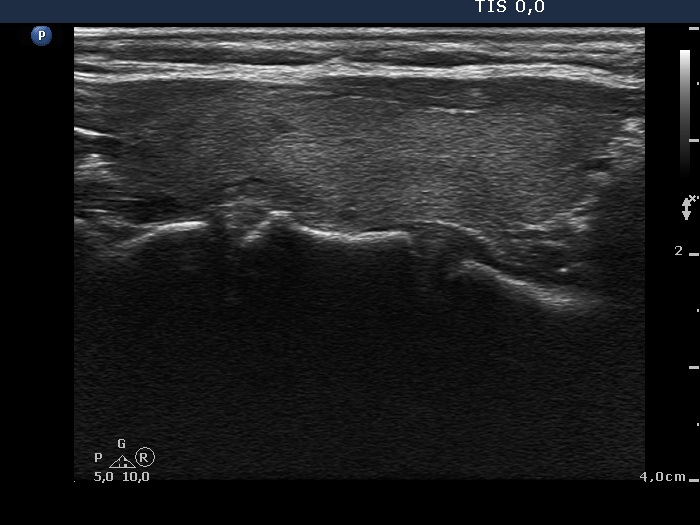

Subacute granulomatous de Quervain's thyroiditis - Case 6.

Five months after initial examination (ultrasonographic picture 7)

Left lobe, longitudinal scan.